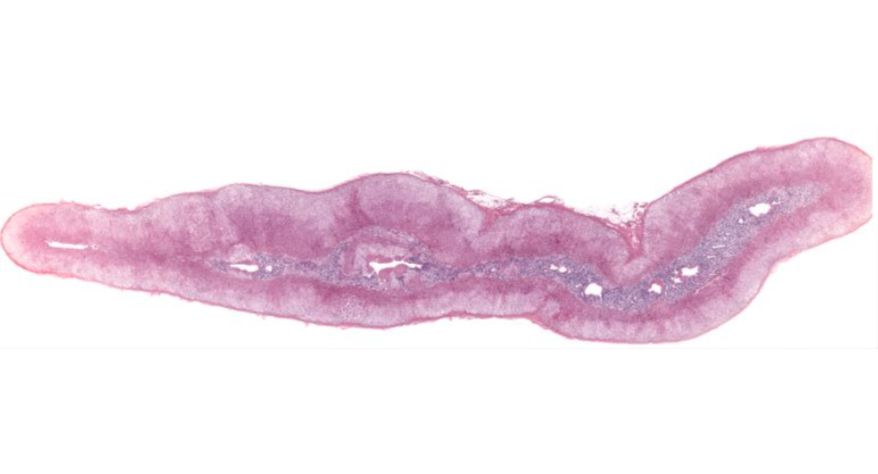

低倍镜观察:1. 被膜:由薄层结缔组织组成。2. 实质:由许多大小不等的滤泡构成。滤泡壁是单层立方上皮细胞,滤泡腔内充满粉红色匀质胶状物,滤泡之间的结缔组织内有丰富的血管。高倍镜观察:1. 滤泡:滤泡壁的单层滤泡上皮细胞一般呈低柱状或立方状,胞质着浅色,细胞核呈圆形。滤泡腔内充满了粉红色匀质胶质。2. 滤泡旁细胞:体积较大,呈圆形或椭圆形;细胞核较大,呈圆形,着色较浅,细胞质染色也较浅。细胞或嵌在滤泡壁上或成团分布于滤泡之间。3. 间质:由结缔组织组成。位于滤泡之间。其中含有丰富的毛细血管及三五成群的滤泡旁细胞。

1.全景图